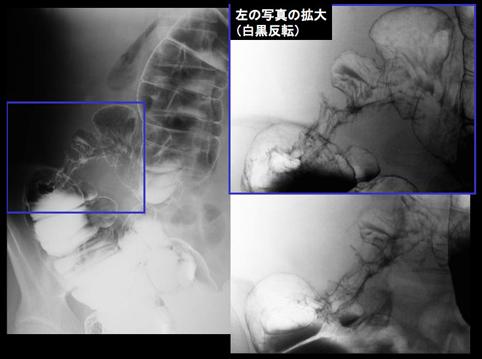

A case of mesenteric panniculitis that induced multiple stenosis of the large intestine.

Fukuoka Pref., MUNAKATA MEDICAL ASSOCIATION (Dr.Miyasaka , Dr.Yoshida)

Inflammatory or ulcerative disease / lesions/Others

Large intestine(Colon)/More than one of the above

X-ray